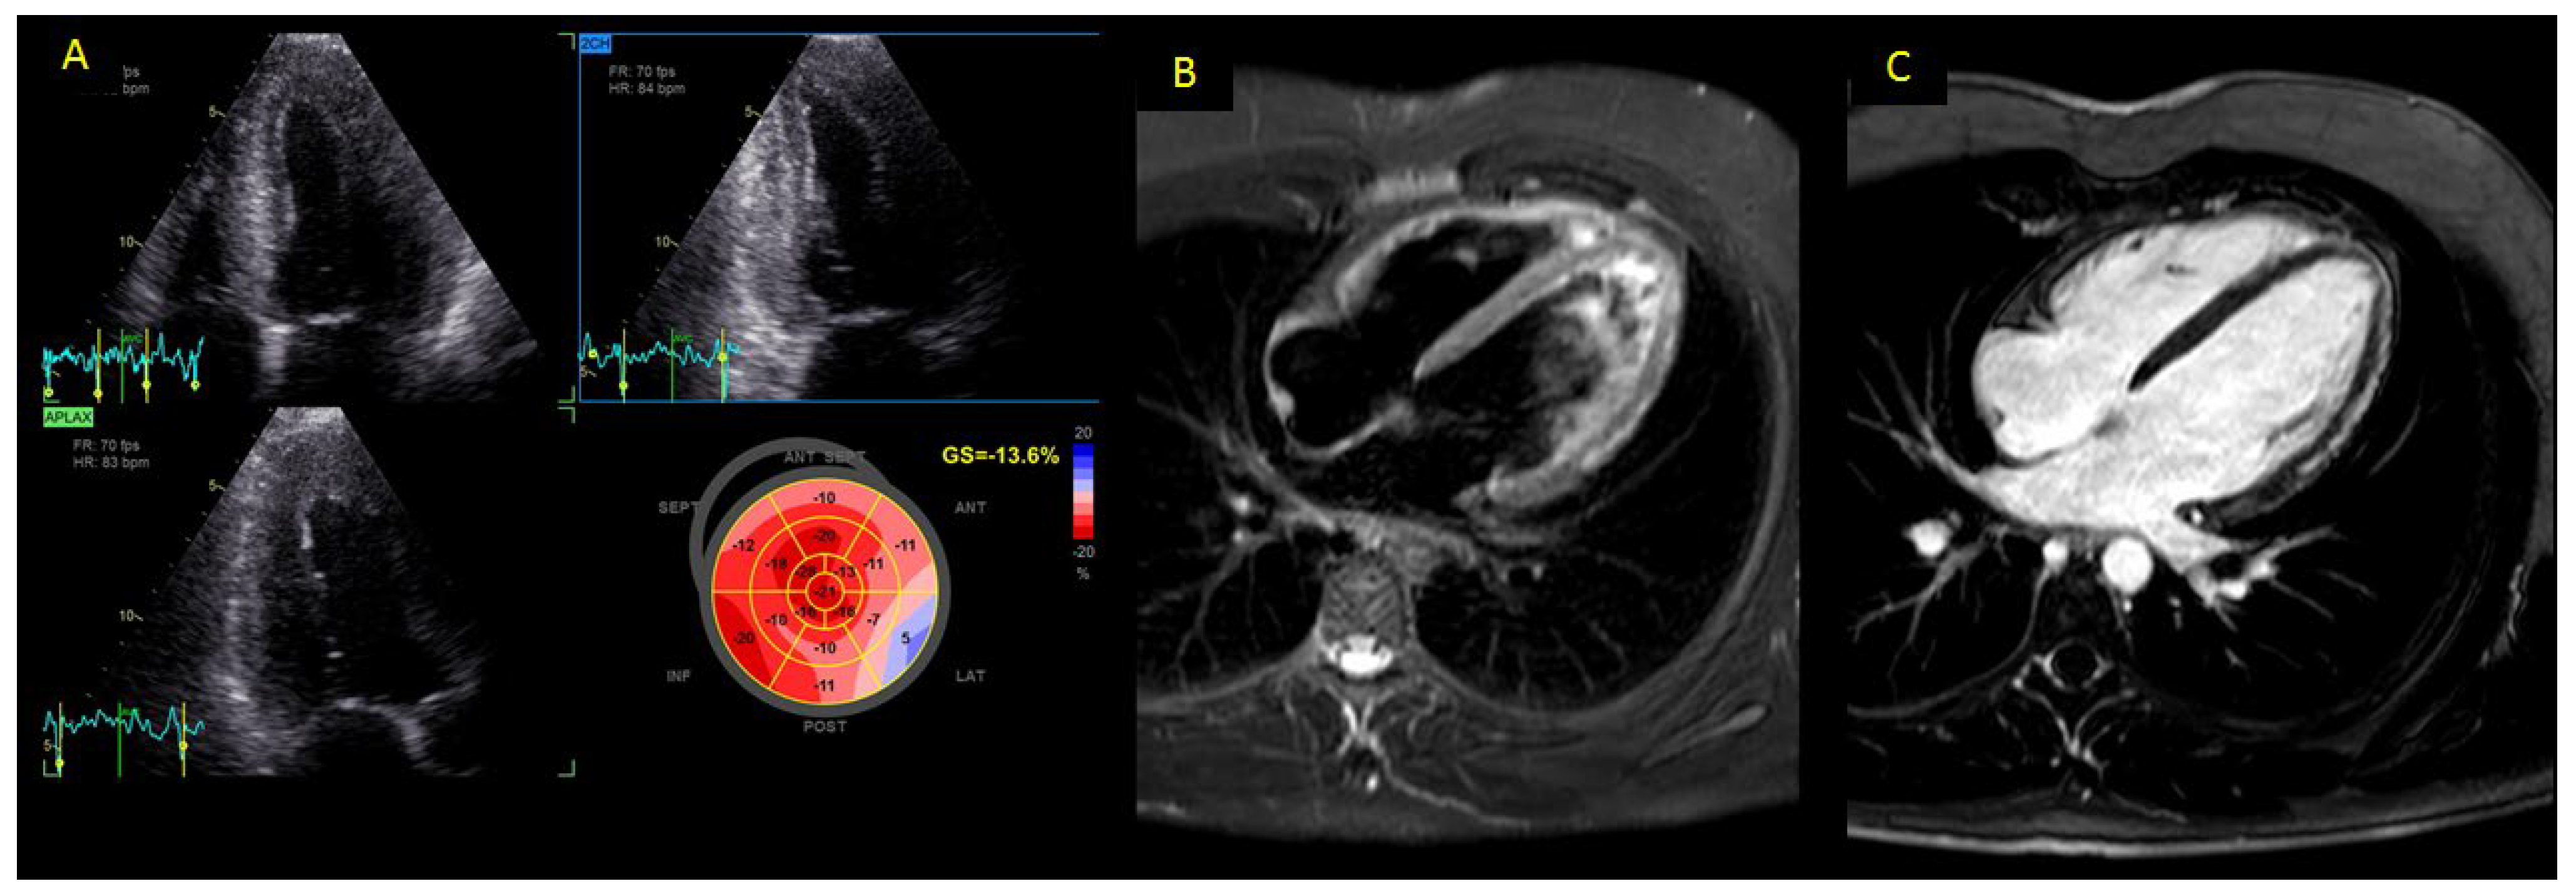

2.4. Cardiovascular Magnetic Resonance (CMR)

| Edema | 55 (100) |

| Hyperemia | 48 (88.3) |

| LGE | 49 (89.1) |

| LGE distribution | |

| -Linear | 48 (87.3) |

| -Patchy | 5 (9.1) |

| -Diffuse | 2 (3.6) |

| LGE pattern | |

| -Epicardial | 39 (70.6) |

| -Mid-wall | 15 (27.6) |

| -Transmural | 1 (1.8) |

| Pericardial effusion | 13 (23.6) |

| TSB, mean ± SD | 2.5 ± 1.3 |